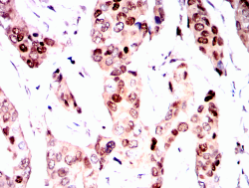

Immunogen:    Purified recombinant fragment of PGR (aa731-909) expressed in E. Coli.

IHC    1/200 - 1/1000